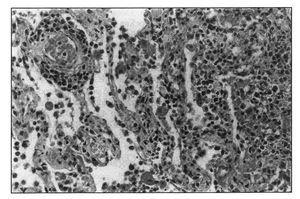

A la exploración física destacaba una masa a nivel de hipocondrio derecho, muy dolorosa a la palpación y un hematoma periumbilical y en flanco izquierdo, con peristaltismo conservado. La Rx de tórax era normal y en la ecografía abdominal se evidenciaba una imagen de ecoestructura heterogénea, fucsiforme, de 11,2 x 8,2 cm, en localización de músculo recto anterior derecho, sugestivo de hematoma (figura 1). En la analítica se objetivo. Htco: 33%, Hb 11 g/dl, Leuc: 8.400/mcl, Cr en plasma. 1,4 mg/dl, Urea: 60 mg/dl, GOT: 55 u/l GPT: 38 u/l, LDH: 743 u/l, BT: 2,8 mg/dl, BD, 2,4 mg/dl. E. coagulación. APTT. 33, I. Quick. 100%, TT: 19,6. Plaq: 128.000/mcl. El test de agregación plaquetaria mostró un déficit de agregación a los inhibidores ADP, colágeno, ácido araquidónico y normalidad a la agregación con ristocetina.

Figura 1. Ecografía abdominal sugestiva de hematoma